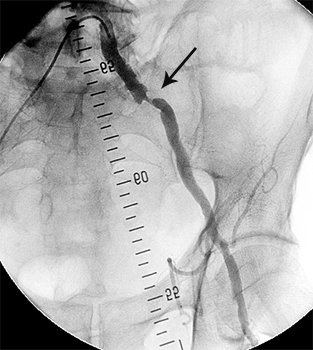

Приклади ангіограм:

стеноз правої ниркової артерії    пухлина підшлункової залози

Ниркова артерія (1), критичне звуження

ниркової артерії, (2) паренхіма нирки (3)